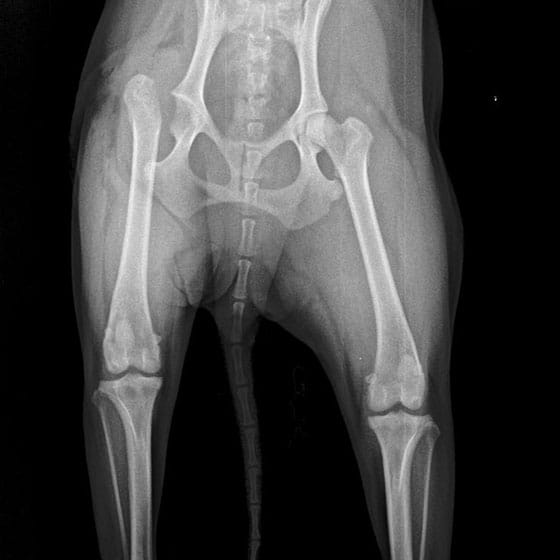

Femoral Head and Neck Ostectomy

- Indications: FHO is considered when pets suffer from chronic or acute hip pain not relieved by other methods. It is also suitable in very specific hip conditions that are or will result in fracture of the hip.

- The femoral head and neck are removed, allowing the muscles and scar tissue to create a supportive pseudo-joint.